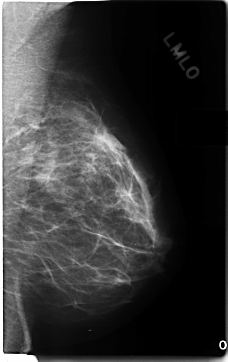

C_0197_1.LEFT_MLO

C_0197_1.LEFT_CC

LEFT_CC LINES 4808 PIXELS_PER_LINE 2496 BITS_PER_PIXEL 12 RESOLUTION 50 NON_OVERLAY

LEFT_MLO LINES 4696 PIXELS_PER_LINE 2952 BITS_PER_PIXEL 12 RESOLUTION 50 NON_OVERLAY